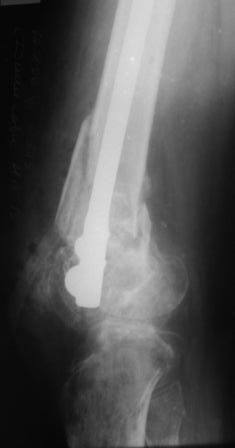

Уважаемые коллеги! Представляю на ваш суд ближйший результаты лечения.

На момент операции не было возможности запечатлеть увиденное, поэтому попытаюсь пересказать.

Первое что пришло в голову по аналогии очень похоже на асептический некроз головки бедра когда головку извлекают при эндопротезировании.Хрящ внутреннего мыщелка бедра был отслоен и изменен,сам мыщелок проминался под пальцем. От блокирования стяжкой отказались. Можно ли это расценить как асептический неркоз внутреннего мыщелка в результате первичной травмы?

Леонид Соломин писал о случае с пателлофеморальным синдесмозом(спасибо), но к сожалению сообщение пришло уже после операции.Прежде мы не встречались с подобным.Во время мобилизации после артролиза, отсечения интремедиуса попытались согнуть колено: хрящ надколенника остался на мыщелках бедра(!). В результате приняли решение удалить надколенник.

Раннее послеоперационное течение не очень спокойное- из раны было сукровичное отделяемое, но сейчас вроде идет на поправку(на фоне интенсивного лечения). В аттаче рентгенограммы.

Жду ваших комментариев!

Рентгенограмма симпатичная...